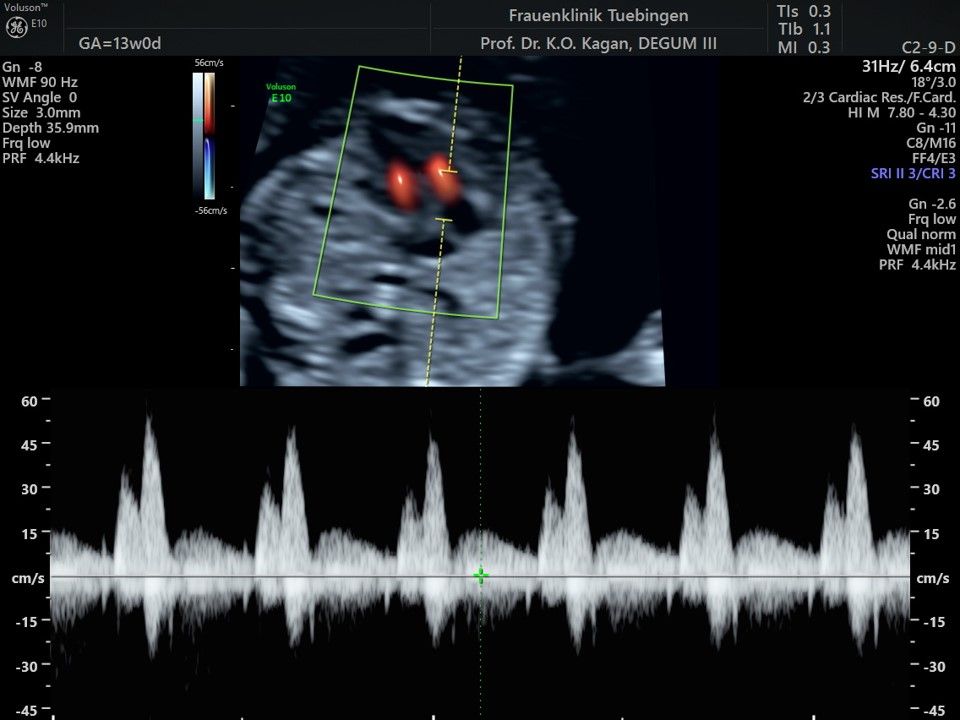

Das Ergebnis der Ultraschalluntersuchung ist wegweisend. Dabei wird der Fet vermessen, die Organe werden untersucht und die sonographischen Marker zur Risikoberechnung für Chromosomenstörungen werden beurteilt. Das sind: die Nackentransparenzdicke, Nasenbein sowie der Blutfluss in der rechten Herzhälfte und im Ductus venosus, einem Gefäß in der Leber des Feten.